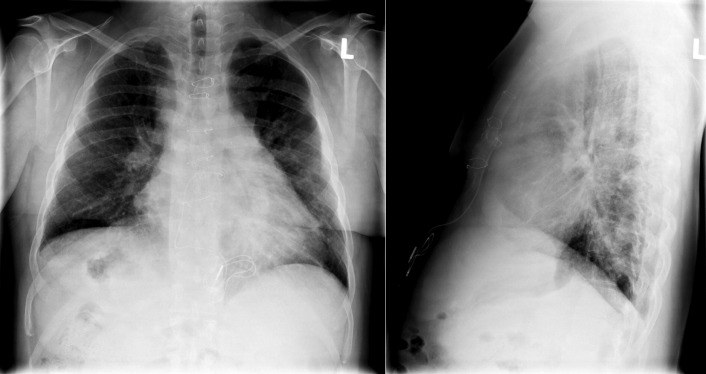

The classic physiology of Eisenmenger syndrome is represented on the chest radiograph by enlargement and centralization (“pruning”) of the pulmonary arterial vasculature, diminished pulmonary venous vasculature, and right heart enlargement.

Situs refers to the position/arrangement of the thoracic and abdominal organs ( Figs 20-1 to 20-5 ). The posteroanterior/frontal chest radiograph is able to depict the location of the heart, the left ventricular apex, the aorta, and the gastric air bubble, and it may thereby determine situs.